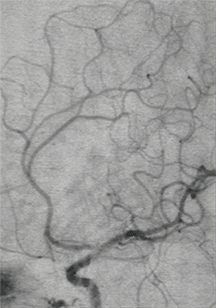

颅脑DSA-3D成像

临床诊断:右侧大脑中动脉分叉部宽颈动脉瘤;右侧大脑中动脉狭窄支架植入术后。

动脉瘤尺寸:2.12*1.95mm

患者动脉瘤瘤颈累及M1分叉部中、下两个干支;且患者阵发性头痛加重,动脉瘤破裂出血的风险较高,需要手术干预。该动脉瘤属相对宽径,单纯弹簧圈栓塞,弹簧圈易脱出,需支架辅助。病人选择支架辅助弹簧圈栓塞治疗技术。